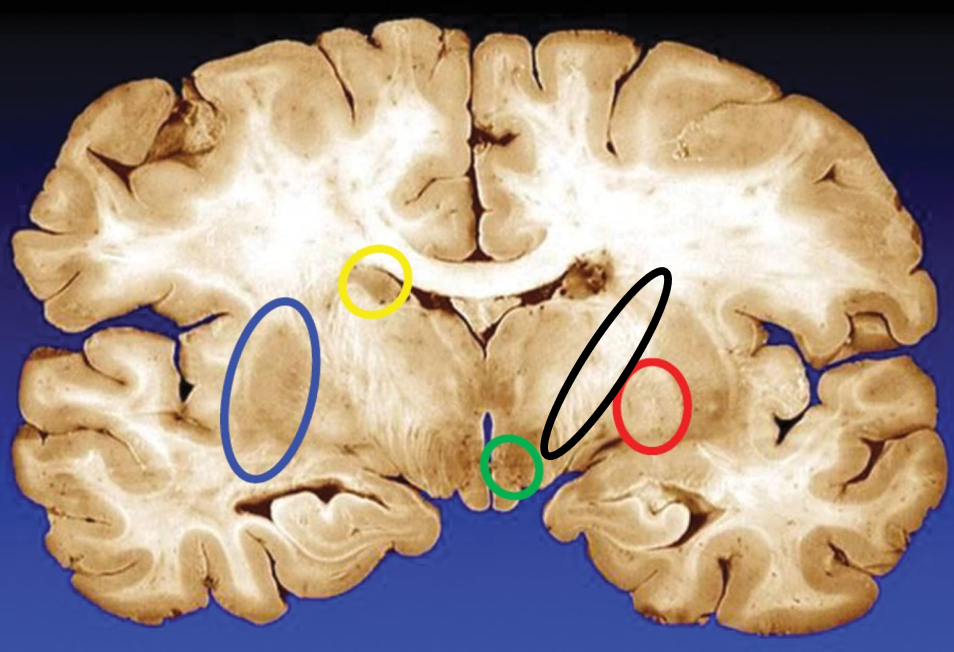

blue

putamen

yellow

caudate

green

subthalamic nuclei

black

internal capsule

red

globus pallidus

name the condition

Huntington’s (reduced caudate)